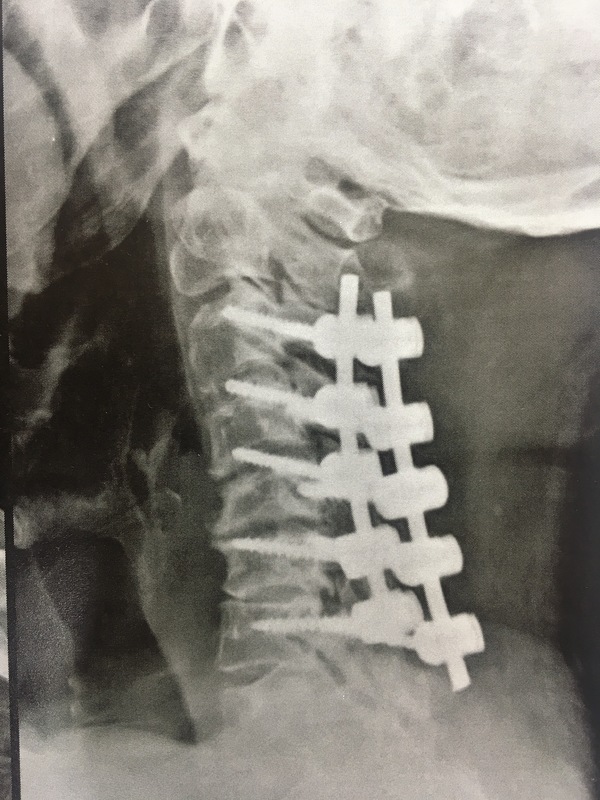

lateral mass fixation done in OPLL.